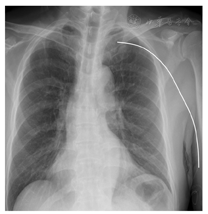

患者,男,64岁,诊断为前列腺癌,既往有高血压、糖尿病病史。入院实验室检查:血常规正常,D-二聚体620 μg/L。2018年3月29日因化疗需要右上臂贵要静脉在超声引导下置入非三向瓣膜单腔4 F PICC(美国昊朗优力捷导管),穿刺、送管均1次成功,导管置入体内45 cm,胸部X线片显示导管尖端位于上腔静脉下段,气管隆突下1椎体。导管留置期间,患者在本院共接受6次静脉化疗(泰素帝、地塞米松联合用药),每次输液前回抽血液通畅,未发现导管内血栓,输液结束10 ml氯化钠注射液脉冲冲管,2 ml肝素氯化钠溶液(浓度10 U/ml)正压封管。治疗间歇期患者在当地医院每7天维护一次,未发生异常情况。2018年8月3日患者完成最后一次化疗,遵医嘱拔管,导管体内留置129 d。护士严格遵守PICC拔管操作流程。拔管初始无阻力,拔出15 cm时突然阻力增大,停止拔管动作,导管回弹,回抽血液通畅,冲洗通畅。胸部X线片显示导管走形及尖端位置见图1。